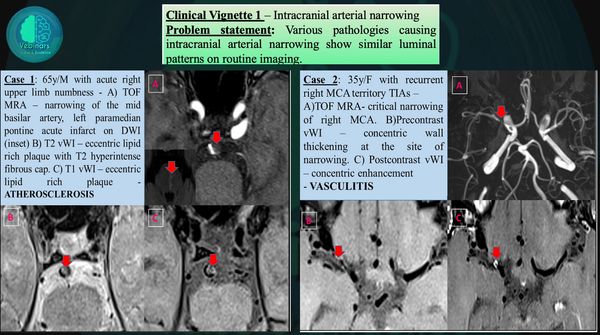

Clues to differentiate neoplastic vs non-neoplastic etiology

Intratumoral hemorrhage

Non-neoplastic hemorrhage